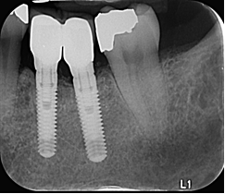

Severe peri radicular

bone loss and

Perio endo lesion

The images describe a clinical case involving a female patient, aged 53 who suffered from severe peri radicular bone loss and Perio endo lesion. The patient underwent full extraction, bone grafting using CoreBone 1000, implant placement, and reconstruction.

Follow-up period lasted 21 months, and the procedure was performed by Professor H. Tal in Israel